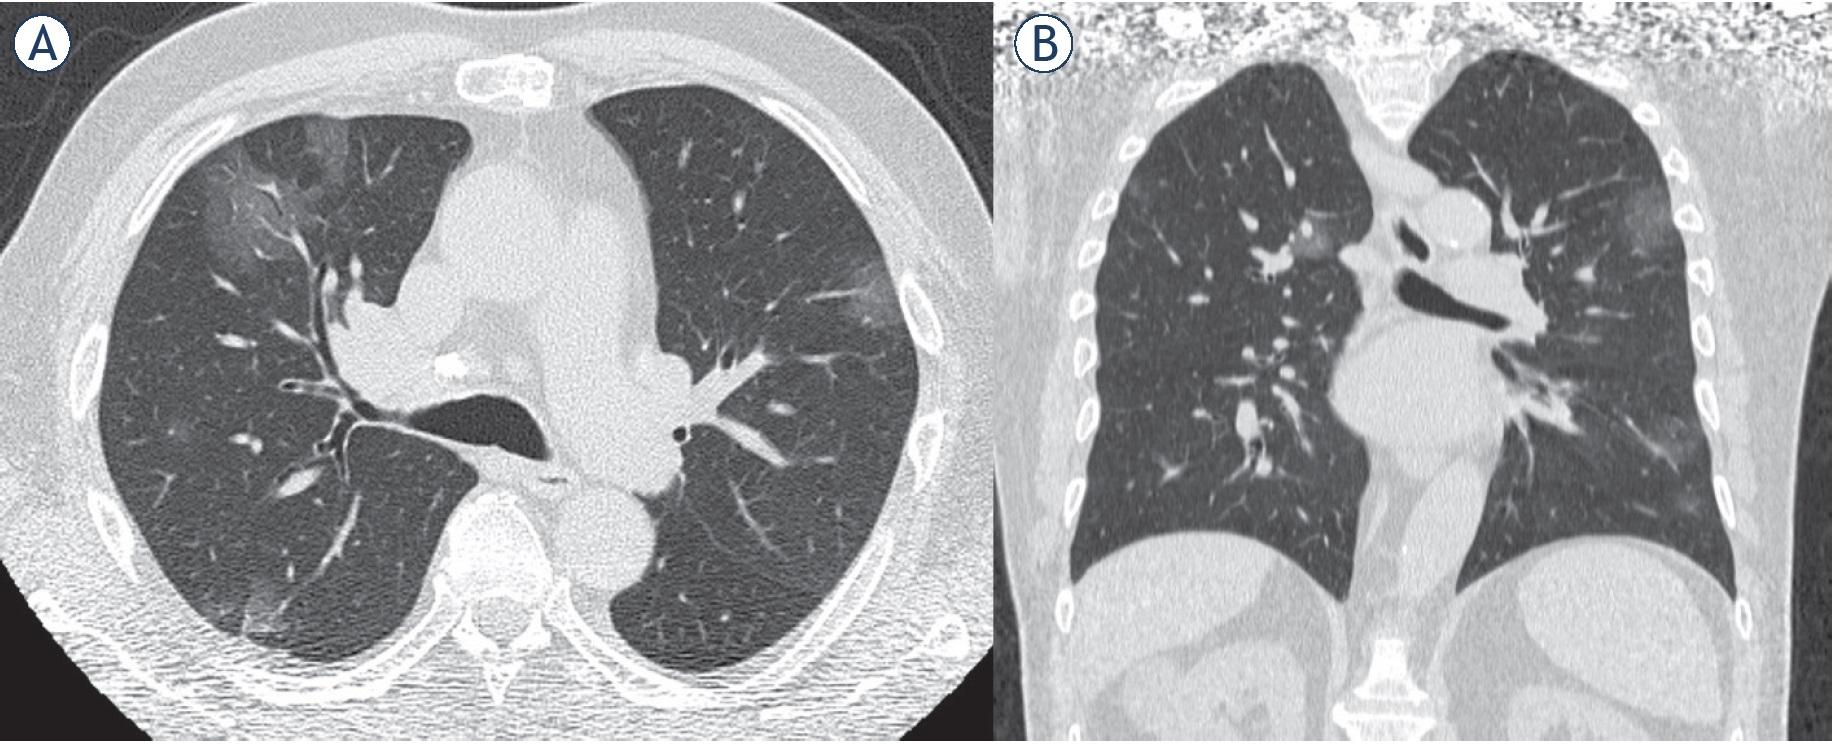

Man 53 y. CT shows multiple focal ground-glass opacities. (A) Axial plane, (B) multiplanar reconstruction in coronal plane.

Ultra-early stage. The stage without clinical symptoms, within 1–2 weeks after the infection. “The typical imaging features are single, double or scattered focal ground-glass opacity, nodules located in central lobule surrounded by patchy ground-glass opacities, patchy consolidation and sign of intra-bronchial air-bronchogram, which was dominant in the middle and lower pleura”7 (Figure 2).